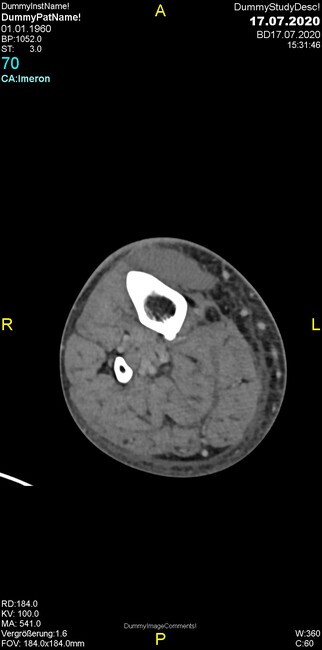

Um welche Modalitäten handelt es sich?

- Röntgen p.a. und lateral, CT coronar Knochenfenster, CT axial Weichgewebsfenster

- Röntgen p.a. und oblique, CT coronar Knochenfenster, CT axial Weichgewebsfenster

- Röntgen p.a. und lateral, CT sagittal Weichgewebsfenster, CT coronar Knochenfenster

- Röntgen p.a. und oblique, CT sagittal Knochenfenster, CT coronar Weichgewebsfenster

- Röntgen p.a. und lateral, CT coronar Weichgewebsfenster, MR axial

Was fällt in der Projektionsradiographie auf?

- Verdichtung im Recessus suprapatellaris

- Aufhellungslinie in Projektion auf die Femurkondylen

- Erhöhter tibialer Slope

- Hypertransparenz tibial

- Subluxationsstellung im Kniegelenk

Was trifft auf den Befund zu?

- Der Befund beschränkt sich auf den Knochen.

- Es besteht hochakuter Handlungsbedarf.

- Der Befund ist tendenziell benigne.

- Der Befund ist tendenziell maligne.

- Der Befund weist einen Zusammenhang zum Patientenalter auf.

Was fällt in der CT im Knochenfenster auf?

- Mediale Gelenkspaltverschmälerung

- Dezente Erosion der fibulären Kortikalis

- Frakturspalt der lateralen Tibiametaphyse

- Weichgewebskalzifikationen lateral angrenzend an den Gelenkspalt

- Osteolyse der Tibiametaphyse unter Beteiligung der Kortikalis